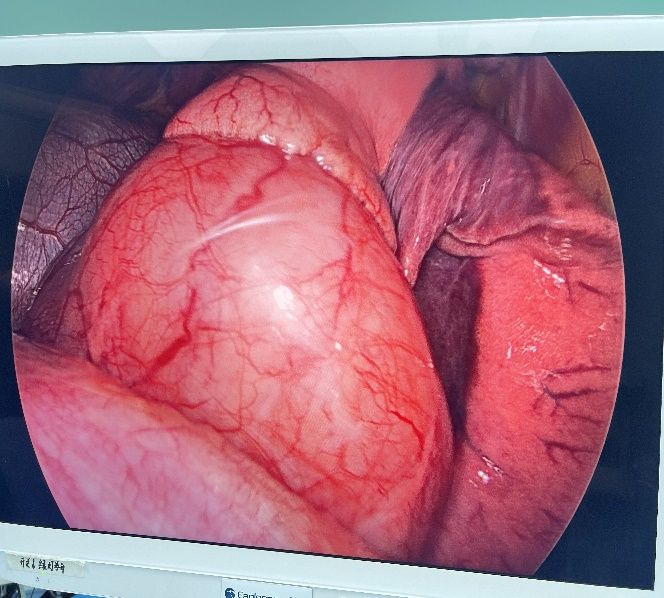

在2024年10月21日,姜建涛主任医师、李建忠副主任、赵丹文医师为小张实施了手术治疗,术中先尝试胸腔镜手术,腔镜下可见食管下段至贲门巨大隆起性病变,姜主任评估后认为腔镜下操作困难大,遂将操作孔延长至5cm行手术,术中发现肿瘤环食管周生长,完整剥除及其困难,但考虑小张年轻,未避免切除食管而对小张以后的生活造成影响,姜主任团队仔细操作,尽可能为小张保住食管,在姜主任及其团队的精心操作下,手术顺利,手术仅历时一个多小时,便将肿瘤完整剥除,剥除下来的肿瘤长径达到了快13cm,试水检查食管粘膜未损伤。在术后第一天查房的时候小张已经能下地活动了,激动的拉着姜主任的手,感谢姜主任为她成功实施手术并保住了食管,感叹姜主任的高超技艺,现小张一切恢复顺利,已康复出院。